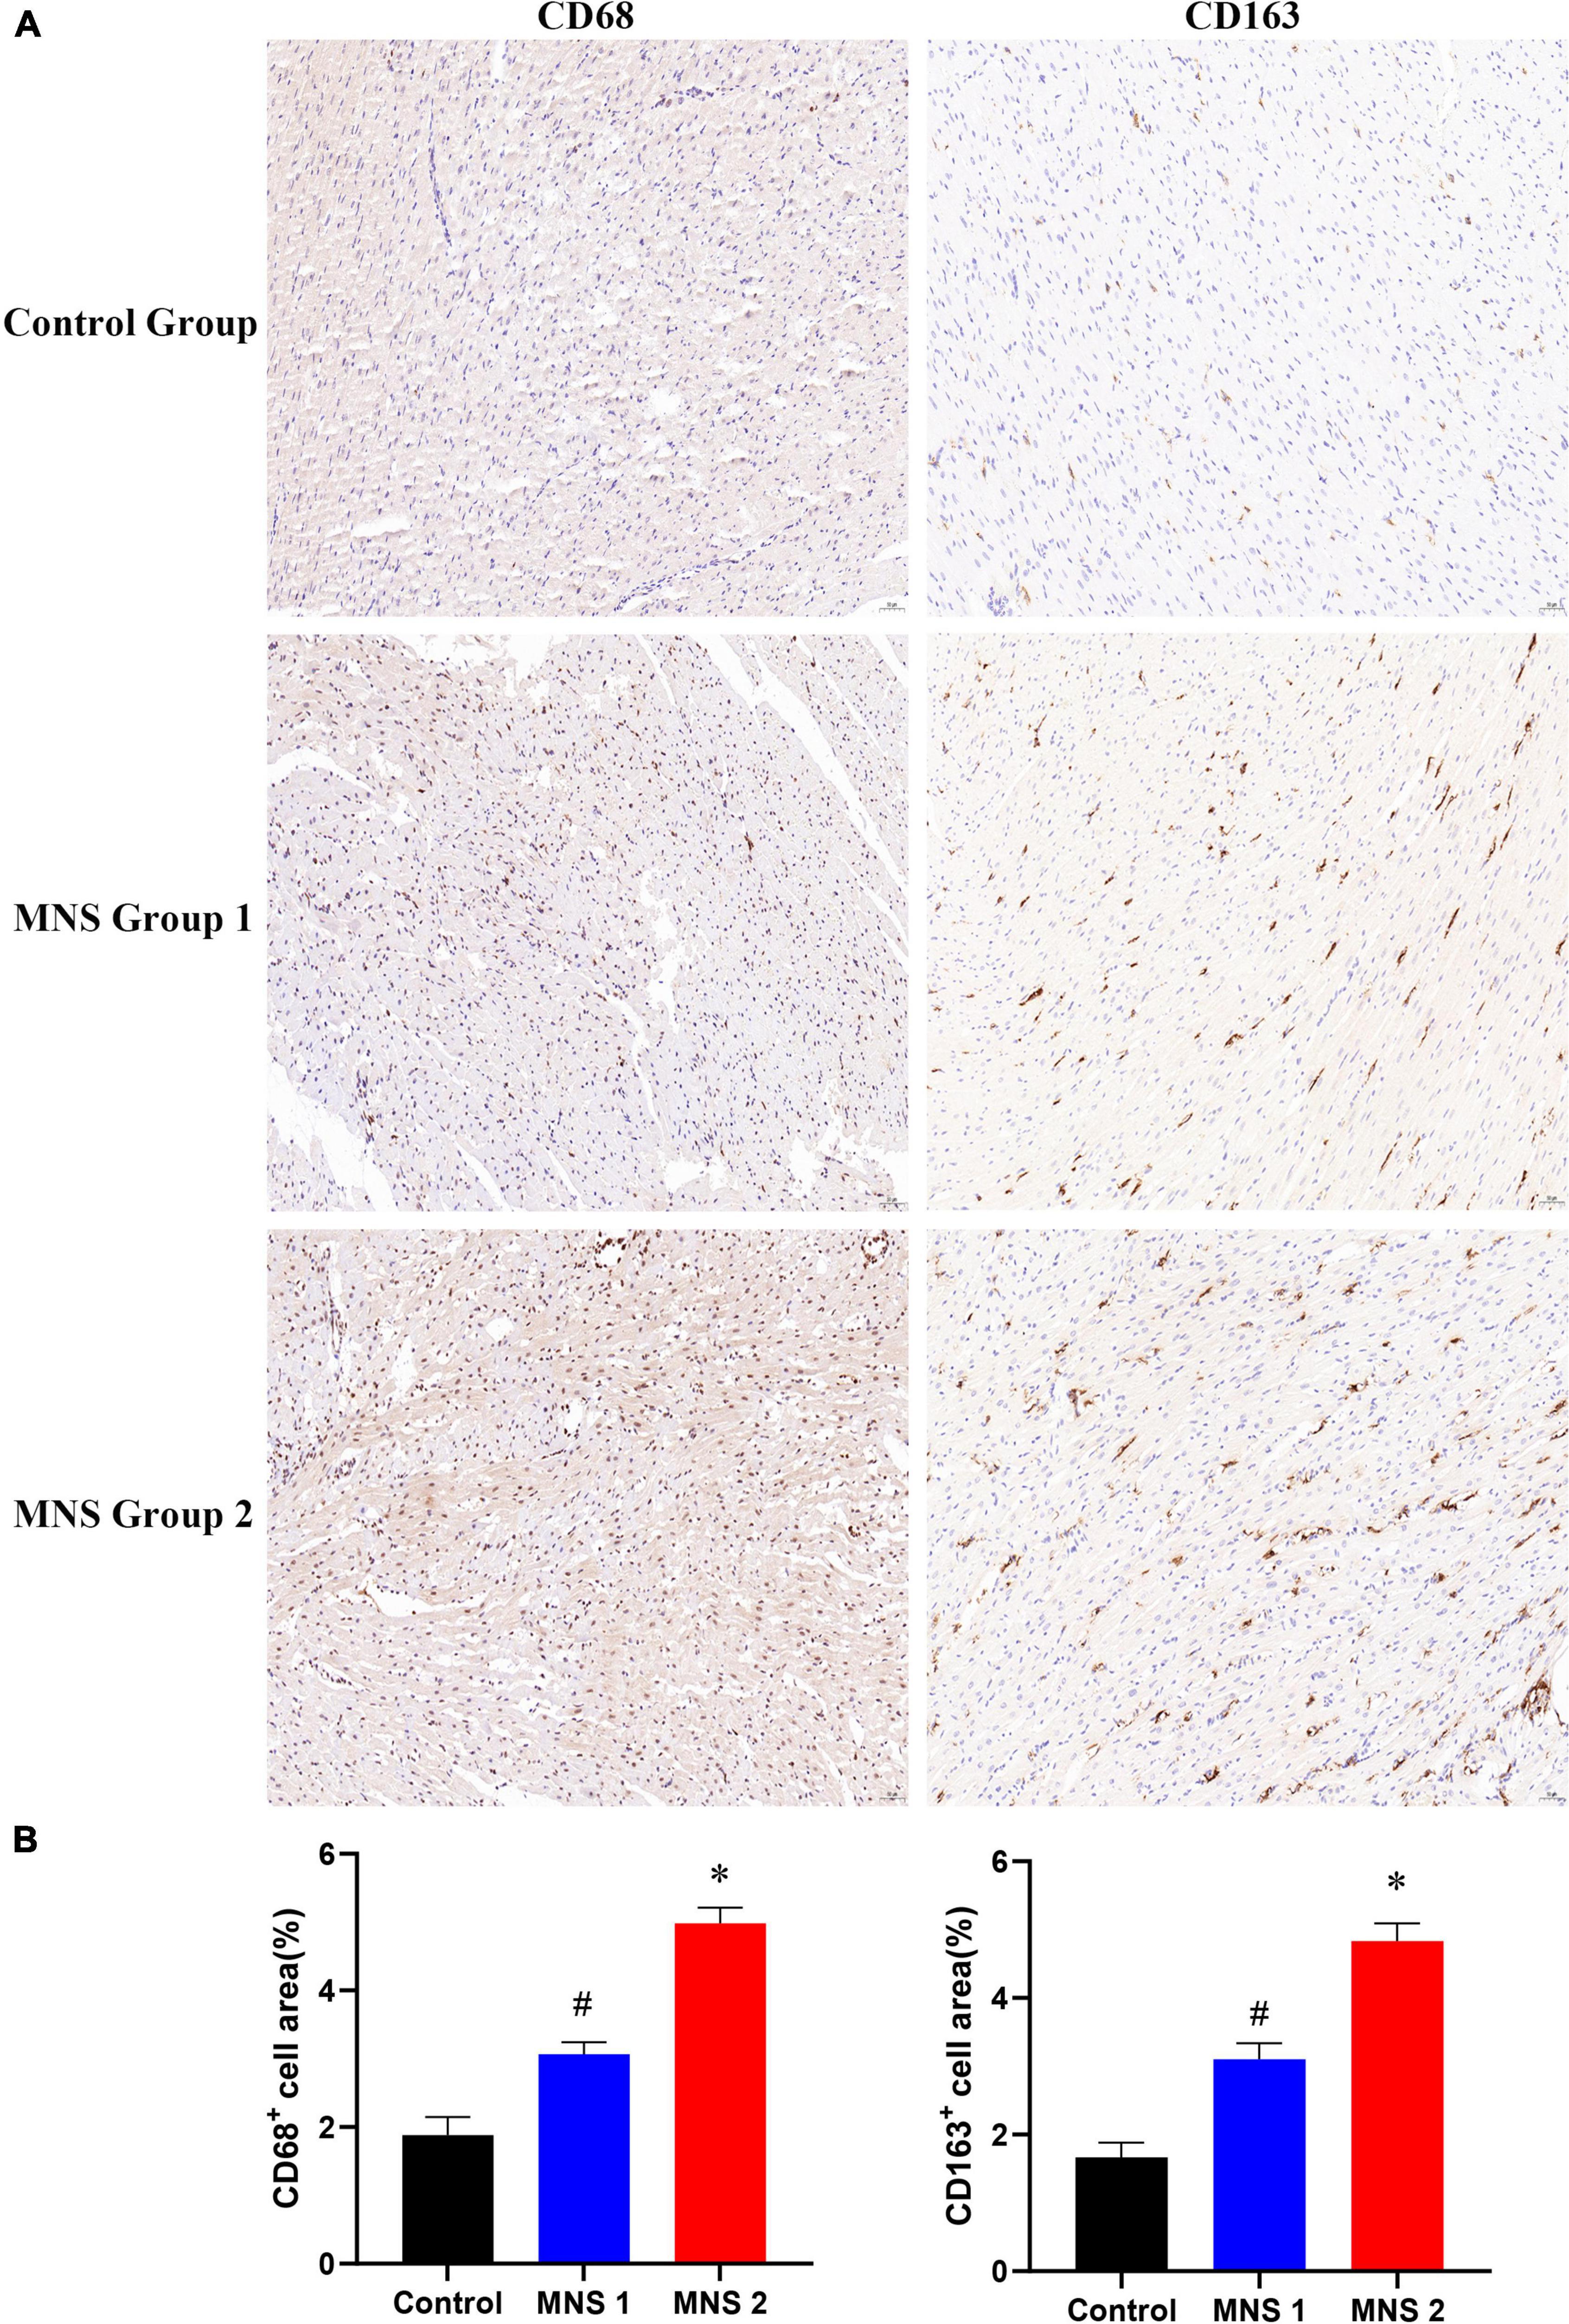

Immunohistochemical analysis

Immunohistochemical staining showed that macrophage markers of CD68 and CD163 were elevated to varying degrees in different groups (Figure 7). The levels of CD68 and CD163 protein in the ventricular samples were significantly higher in the MNS group 2 than in the control group (CD68: 4.98 ± 0.23 vs. 1.88 ± 0.26, P < 0.01; CD163: 4.83 ± 0.26 vs. 1.67 ± 0.22, P < 0.01) and in the MNS group 1 (CD68: 4.98 ± 0.23 vs. 3.07 ± 0.18, P < 0.01; CD163: 4.83 ± 0.26 vs. 3.1 ± 0.24, P < 0.01). Compared to the control group, CD68 and CD163 protein expressions were higher in the MNS group 1 (CD68: 3.07 ± 0.18 vs. 1.88 ± 0.26, P < 0.01; CD163: 3.1 ± 0.24 vs. 1.67 ± 0.22, P < 0.01).

Figure 7. CD68 and CD163 immunohistochemistry (IHC) of left ventricular myocardial tissue in each group. (A,B) Representative examples and quantitative analyses of CD68 and CD163 expression in the control, MNS group 1, and MNS group 2 dogs. #P < 0.01 vs. control group and MNS group 2; *P < 0.01 vs. control group.